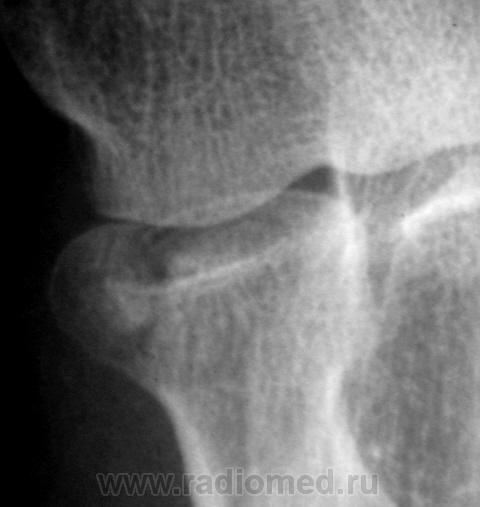

Травма. Пациент направлен на рентгенографию локтевого сустава.

перелом головки луча, встречается не так и часто.

Внутрисуставной,краевой перелом головки лучевой кости.